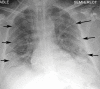

The coronavirus disease 2019 (COVID-19) pandemic is a global health care emergency. Although reverse-transcription polymerase chain reaction testing is the reference standard method to identify patients with COVID-19 infection, chest radiography and CT play a vital role in the detection and management of these patients. Prediction models for COVID-19 imaging are rapidly being developed to support medical decision making. However, inadequate availability of a diverse annotated data set has limited the performance and generalizability of existing models. To address this unmet need, the RSNA and Society of Thoracic Radiology collaborated to develop the RSNA International COVID-19 Open Radiology Database (RICORD). This database is the first multi-institutional, multinational, expert-annotated COVID-19 imaging data set. It is made freely available to the machine learning community as a research and educational resource for COVID-19 chest imaging. Pixel-level volumetric segmentation with clinical annotations was performed by thoracic radiology subspecialists for all COVID-19-positive thoracic CT scans. The labeling schema was coordinated with other international consensus panels and COVID-19 data annotation efforts, the European Society of Medical Imaging Informatics, the American College of Radiology, and the American Association of Physicists in Medicine. Study-level COVID-19 classification labels for chest radiographs were annotated by three radiologists, with majority vote adjudication by board-certified radiologists. RICORD consists of 240 thoracic CT scans and 1000 chest radiographs contributed from four international sites. It is anticipated that RICORD will ideally lead to prediction models that can demonstrate sustained performance across populations and health care systems.